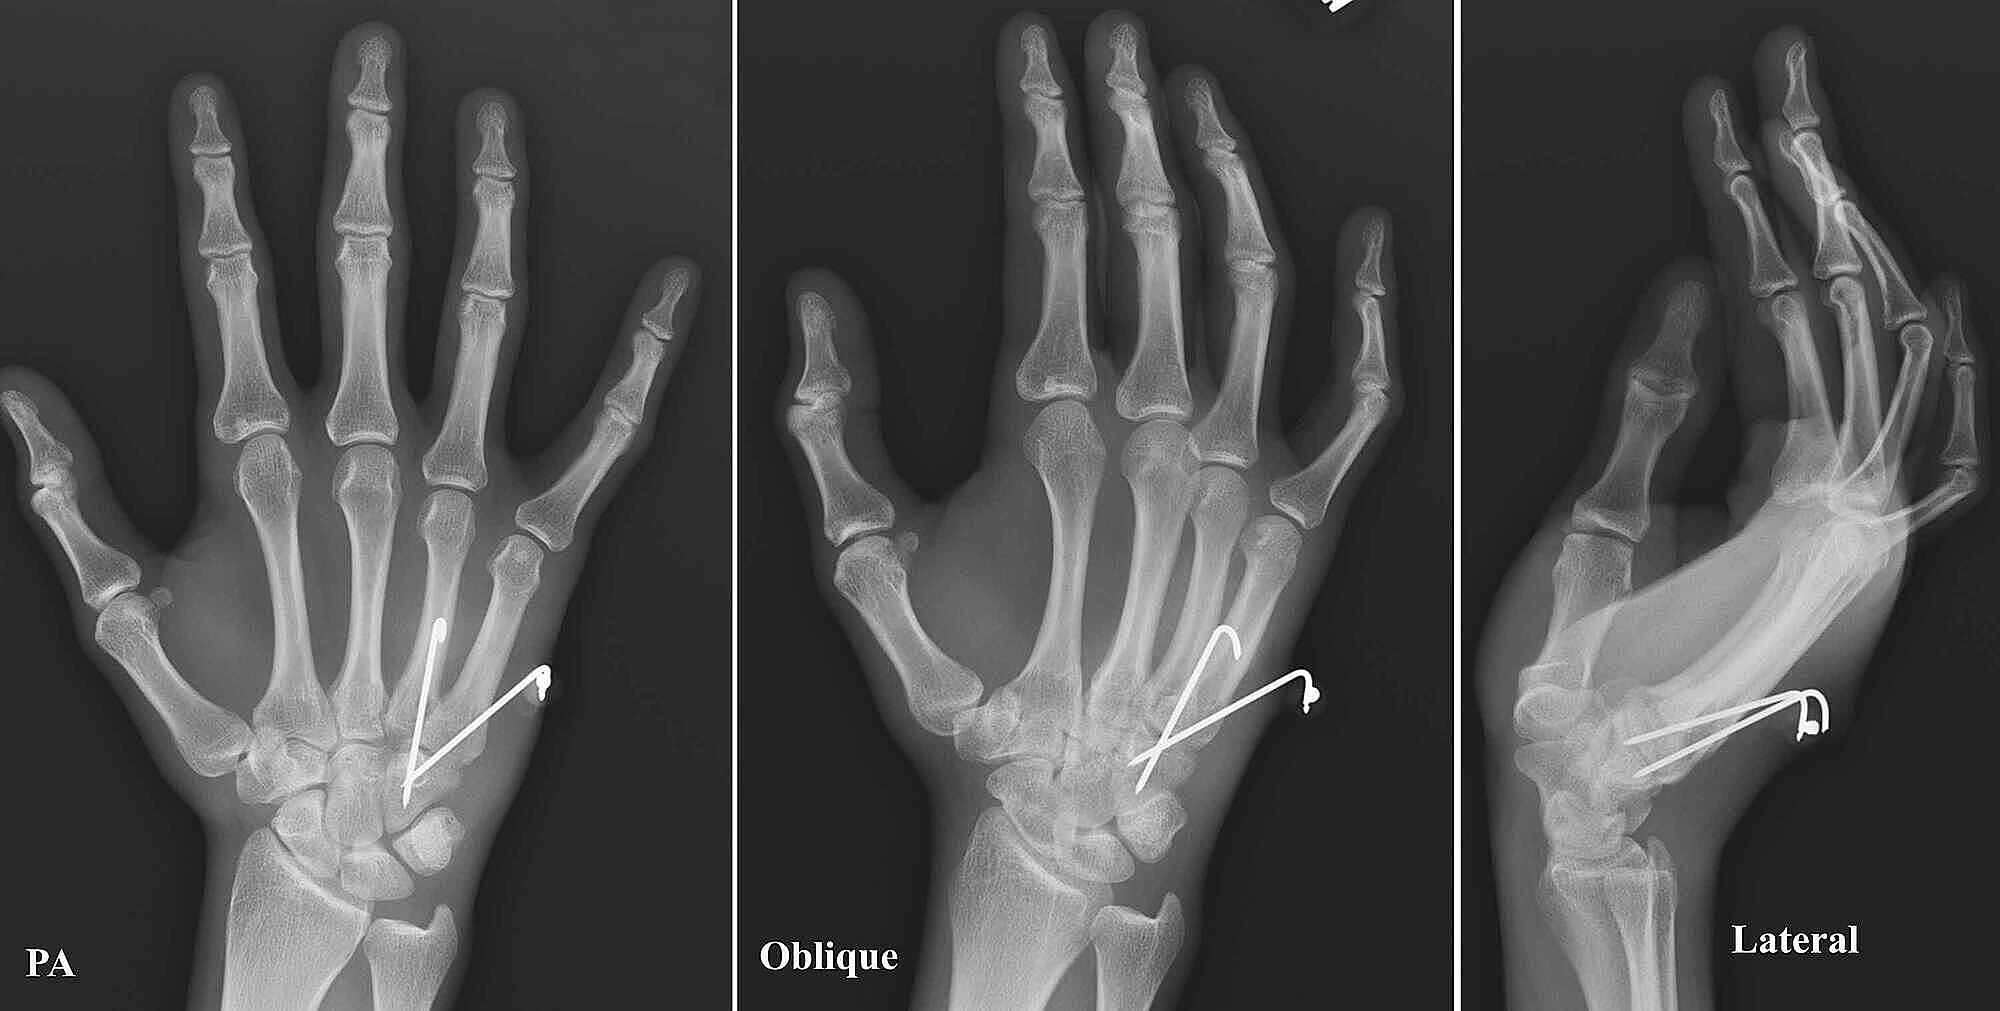

Fourth and fifth carpometacarpal joint dislocations Image Basal Carpometacarpal Joint Dislocation Although rare, thumb carpometacarpal (cmc) joint dislocations can. Thumb arthritis is common with aging and occurs when cartilage wears away from the ends of the bones that form the joint at the. Thumb carpometacarpal (cmc) joint dislocations are rare, with a prevalence of less than 1% of all hand injuries. Dislocation of the thumb carpometacarpal (cmc) joint is a rare. Basal Carpometacarpal Joint Dislocation.

Patient with fourth and fifth carpometacarpal dislocation after car Basal Carpometacarpal Joint Dislocation Thumb arthritis is common with aging and occurs when cartilage wears away from the ends of the bones that form the joint at the. Up to 15% of the population older than 30 years suffers from symptomatic thumb carpometacarpal (cmc) osteoarthritis (oa), with. Thumb carpometacarpal (cmc) joint dislocations are rare, with a prevalence of less than 1% of all hand. Basal Carpometacarpal Joint Dislocation.